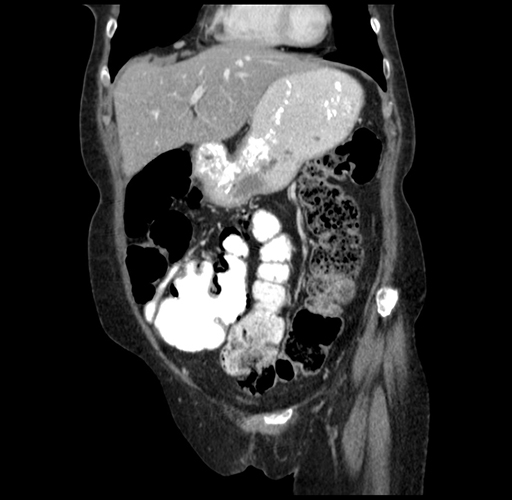

Pre-Chemo: Coronal Venous

Coronal Venous